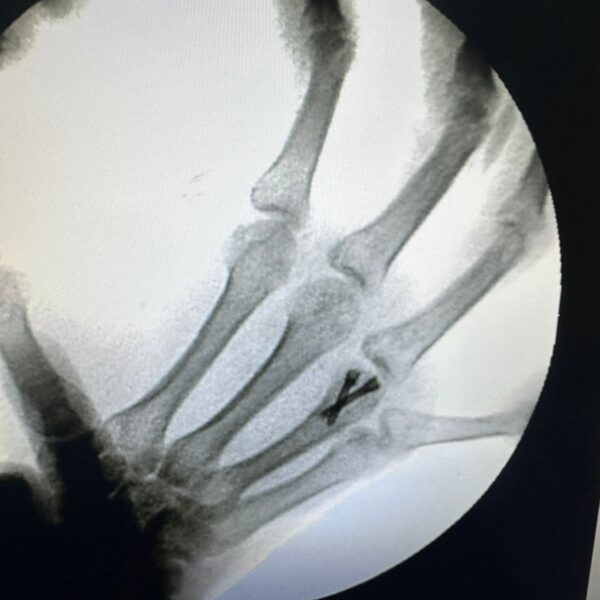

Moments That Mark Meaningful Recovery

Witness real patient transformations at The Ortho Clinic through images that reflect successful treatments and restored mobility.